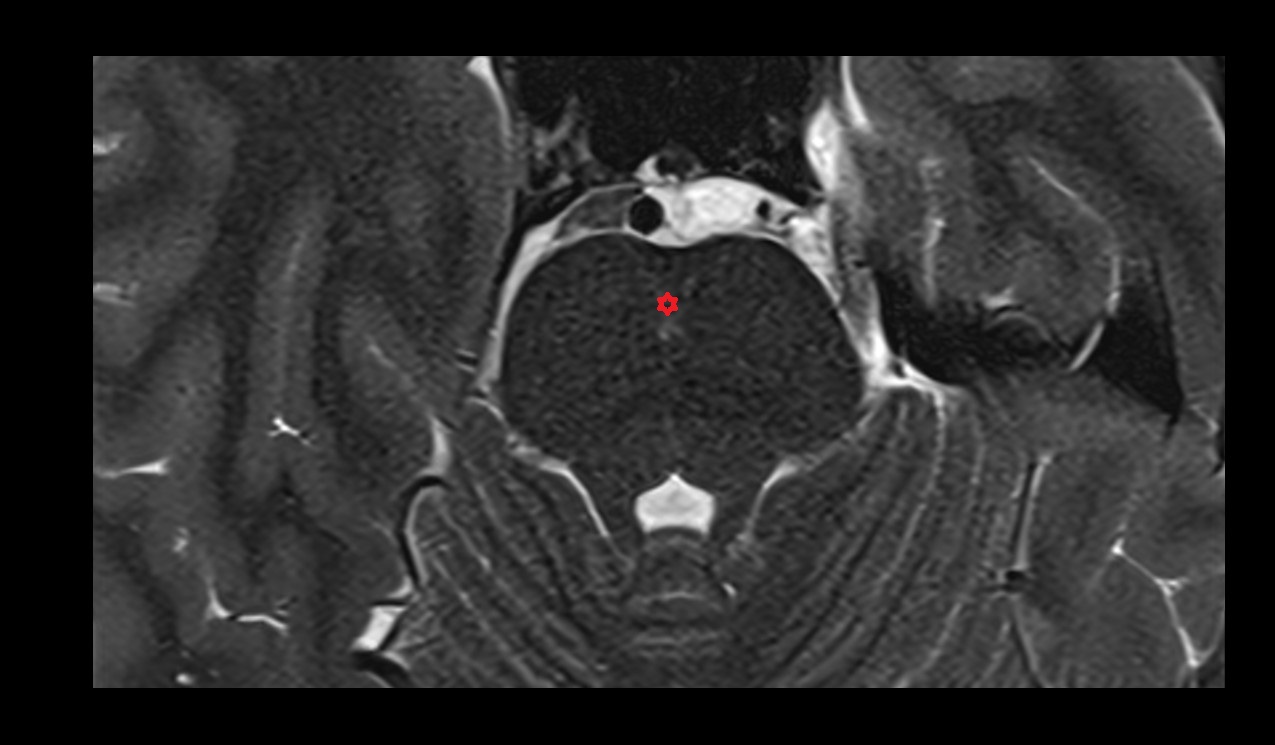

- Peripheral zone of prostate

- Anterior Fibromuscular Stroma of prostate

- Central zone of prostate

- Transitional zone of prostate